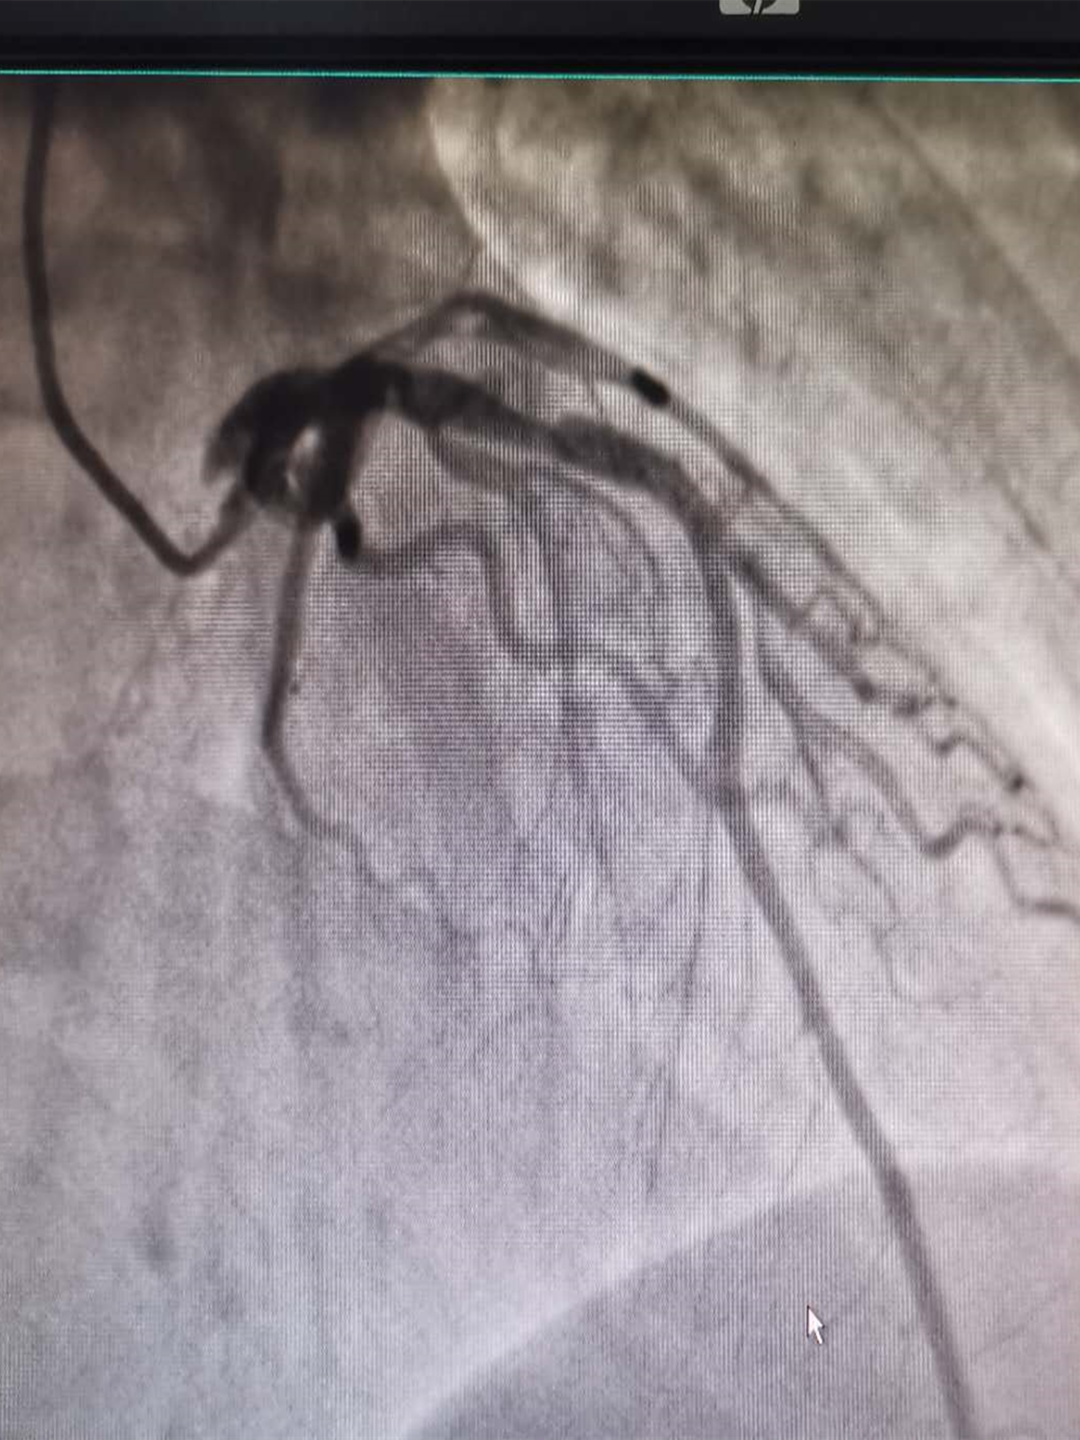

管腔中度狭窄,狭窄程度50%~70%,属于临界病变,这种情况最难判断,因为它可能会引起心肌缺血的各种症状,一般建议行运动平板试验、负荷心肌核素或心肌灌注MRI等功能学检查,诊断是否存在心肌缺血,也可以直接进行冠脉造影检查,明确冠脉狭窄情况,术中可以同时进行压力导丝或血管内超声等更精确的检查;

重度管腔狭窄,狭窄程度≥70%,这是严重冠心病的标志,一般建议患者行冠脉造影检查,也可寻找心肌缺血的证据。